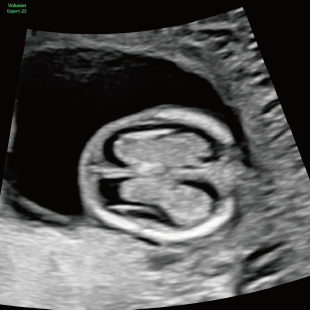

Voluson Expert 22®(GEHealthcare)という産婦人科領域におけるハイエンド超音波診断装置を使用しています。 従来機種と比べ、より高精細な画像描出性能と高度な解析機能を備えており、 胎児の発育や形態をより詳細に観察することが可能です。

超音波診断装置 Voluson Expert 22

初期スクリーニングでは、首の後ろのむくみ(Nuchal translucency: NT)や鼻の骨、心臓まわりの血流などを確認し、胎児の体の特徴や発育の様子を丁寧に観察します。 これらの所見は、染色体数の変化と関連することがある特徴として知られており、21トリソミー/18トリソミー/13トリソミーなどの染色体変化の可能性を評価する指標となります。(本検査のみで確定診断はできません) また観察可能な範囲において脳や脊椎、心臓、消化管、手足などに大きな形態の変化がないかについても確認を行います。